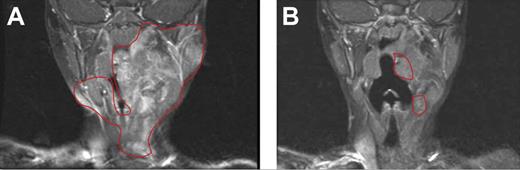

On the basis of these murine experiments implicating c-kit–dependent Nf1+/− marrow cells and the efficacy of imatinib mesylate, clinicians treated a 3-year-old girl with a highly vascularized, nonresectable, and progressively growing neurofibroma. The girl presented as an infant with several hallmark signs of NF1 and a histologically confirmed neurofibroma first appearing at 6 months of age. The tumor had progressively enlarged to encompass the left floor of her mouth, tongue, and mastoid bone and was encasing her carotid artery and jugular vein. At the time of treatment, the tumor had severely compressed her airway, leading to drooling, sleeplessness, and anorexia. After discussing the risks and potential benefits of experimental medical therapy with her physician and her parents, the patient received 350 mg/m2/dose imatinib mesylate. After 3 months of treatment, magnetic resonance imaging showed a remarkable 70% reduction in tumor volume, and the complications associated with the airway compression had resolved. After the tumor ceased its regression and appeared stable, treatment was terminated.23 The patient remains stable and in relatively good health (Figure 6). Encouraged by the mouse model and the successful medical treatment of this index patient, a phase 2 clinical trial involving patients with NF1 with highly morbid neurofibromas has been initiated.

Evaluation of imatinib mesylate efficacy in an index patient with a plexiform neurofibroma. Coronal magnetic resonance imaging scans (T1-weighted images with gadolinium contrast and fat saturation) of the head and oropharynx of a patient with NF1 patient with a plexiform neurofibroma before (A) and 3 months after (B) treatment with imatinib mesylate. The region of the tumor in the respective images is indicated. Reprinted from Yang et al23 with permission from Elsevier.